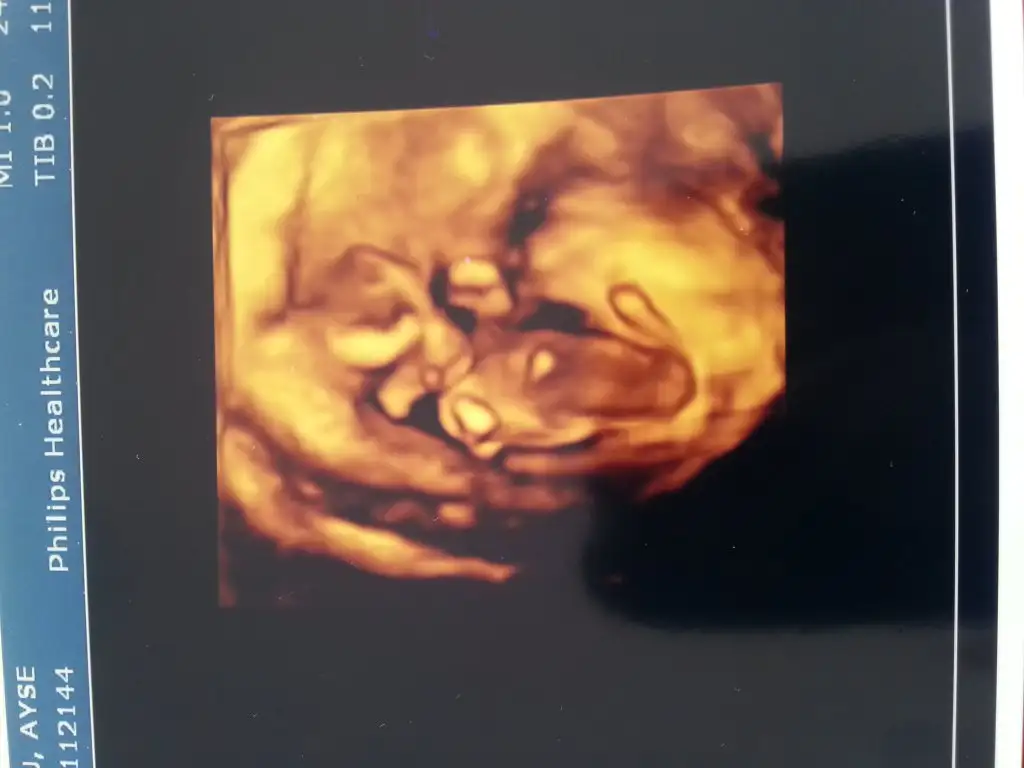

Ay hadi bakalim.. benim de elimde ultrason fotografi var.. ben anliyorum ama insanlar hani kafasi nerde, pipisi nerde deyince şaşırıyorum.. Nasil goremiyorlar? Hayret yaniopera ? nasılmış Figen Hanım test ettin mi? cinsiyet falan söyledi mi?